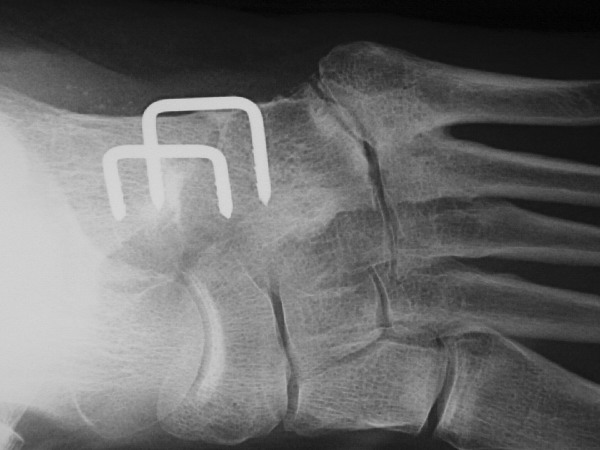

What if patients do require surgery? True cuboid syndrome surgical therapy deals with stabilization of the joint. Three options exist for cuboid stabilization. The treatment options depend on the patient and how willing he or she is to consider further surgery if more conservative surgical cases do not work. The first surgical procedure choice is an arthroscopy of the cuboid-calcaneus joint with a capsular shrinkage of the plantar ligaments. One would do this with an arthroscopic shrinkage device usually used in shoulder stabilization. The procedure takes some time to learn but is fairly simple to perform. Two months of stabilization with casting and nonweightbearing is necessary to allow for added stabilization. The second type of surgical option is a fresh frozen cadaveric tendon stabilization of the calcaneocuboid joint. One would essentially do this through a weave type procedure in which one weaves a tendon about the lateral joint so it can act as a ligamentous stabilizer of the joint. The final and most definitive procedure is a fusion of the calcaneocuboid joint. The procedure is not very difficult to perform and does not cause much stiffness or loss of function of the foot or ankle. It is essential to perform rigid internal or external fusion as the rate of non-union is high in this joint when compared to other rearfoot fusions due to the increased motion associated with this joint. What about the fourth and fifth metatarsocuboid joint? Be very cautious fusing these joints as the rate of non-union is high. Also be aware that these patients sometimes have postoperative pain due to the increased demand for motion at these joints. If there is severe degeneration of these joints, it may be better to perform an arthroplasty of the joints instead of a fusion.